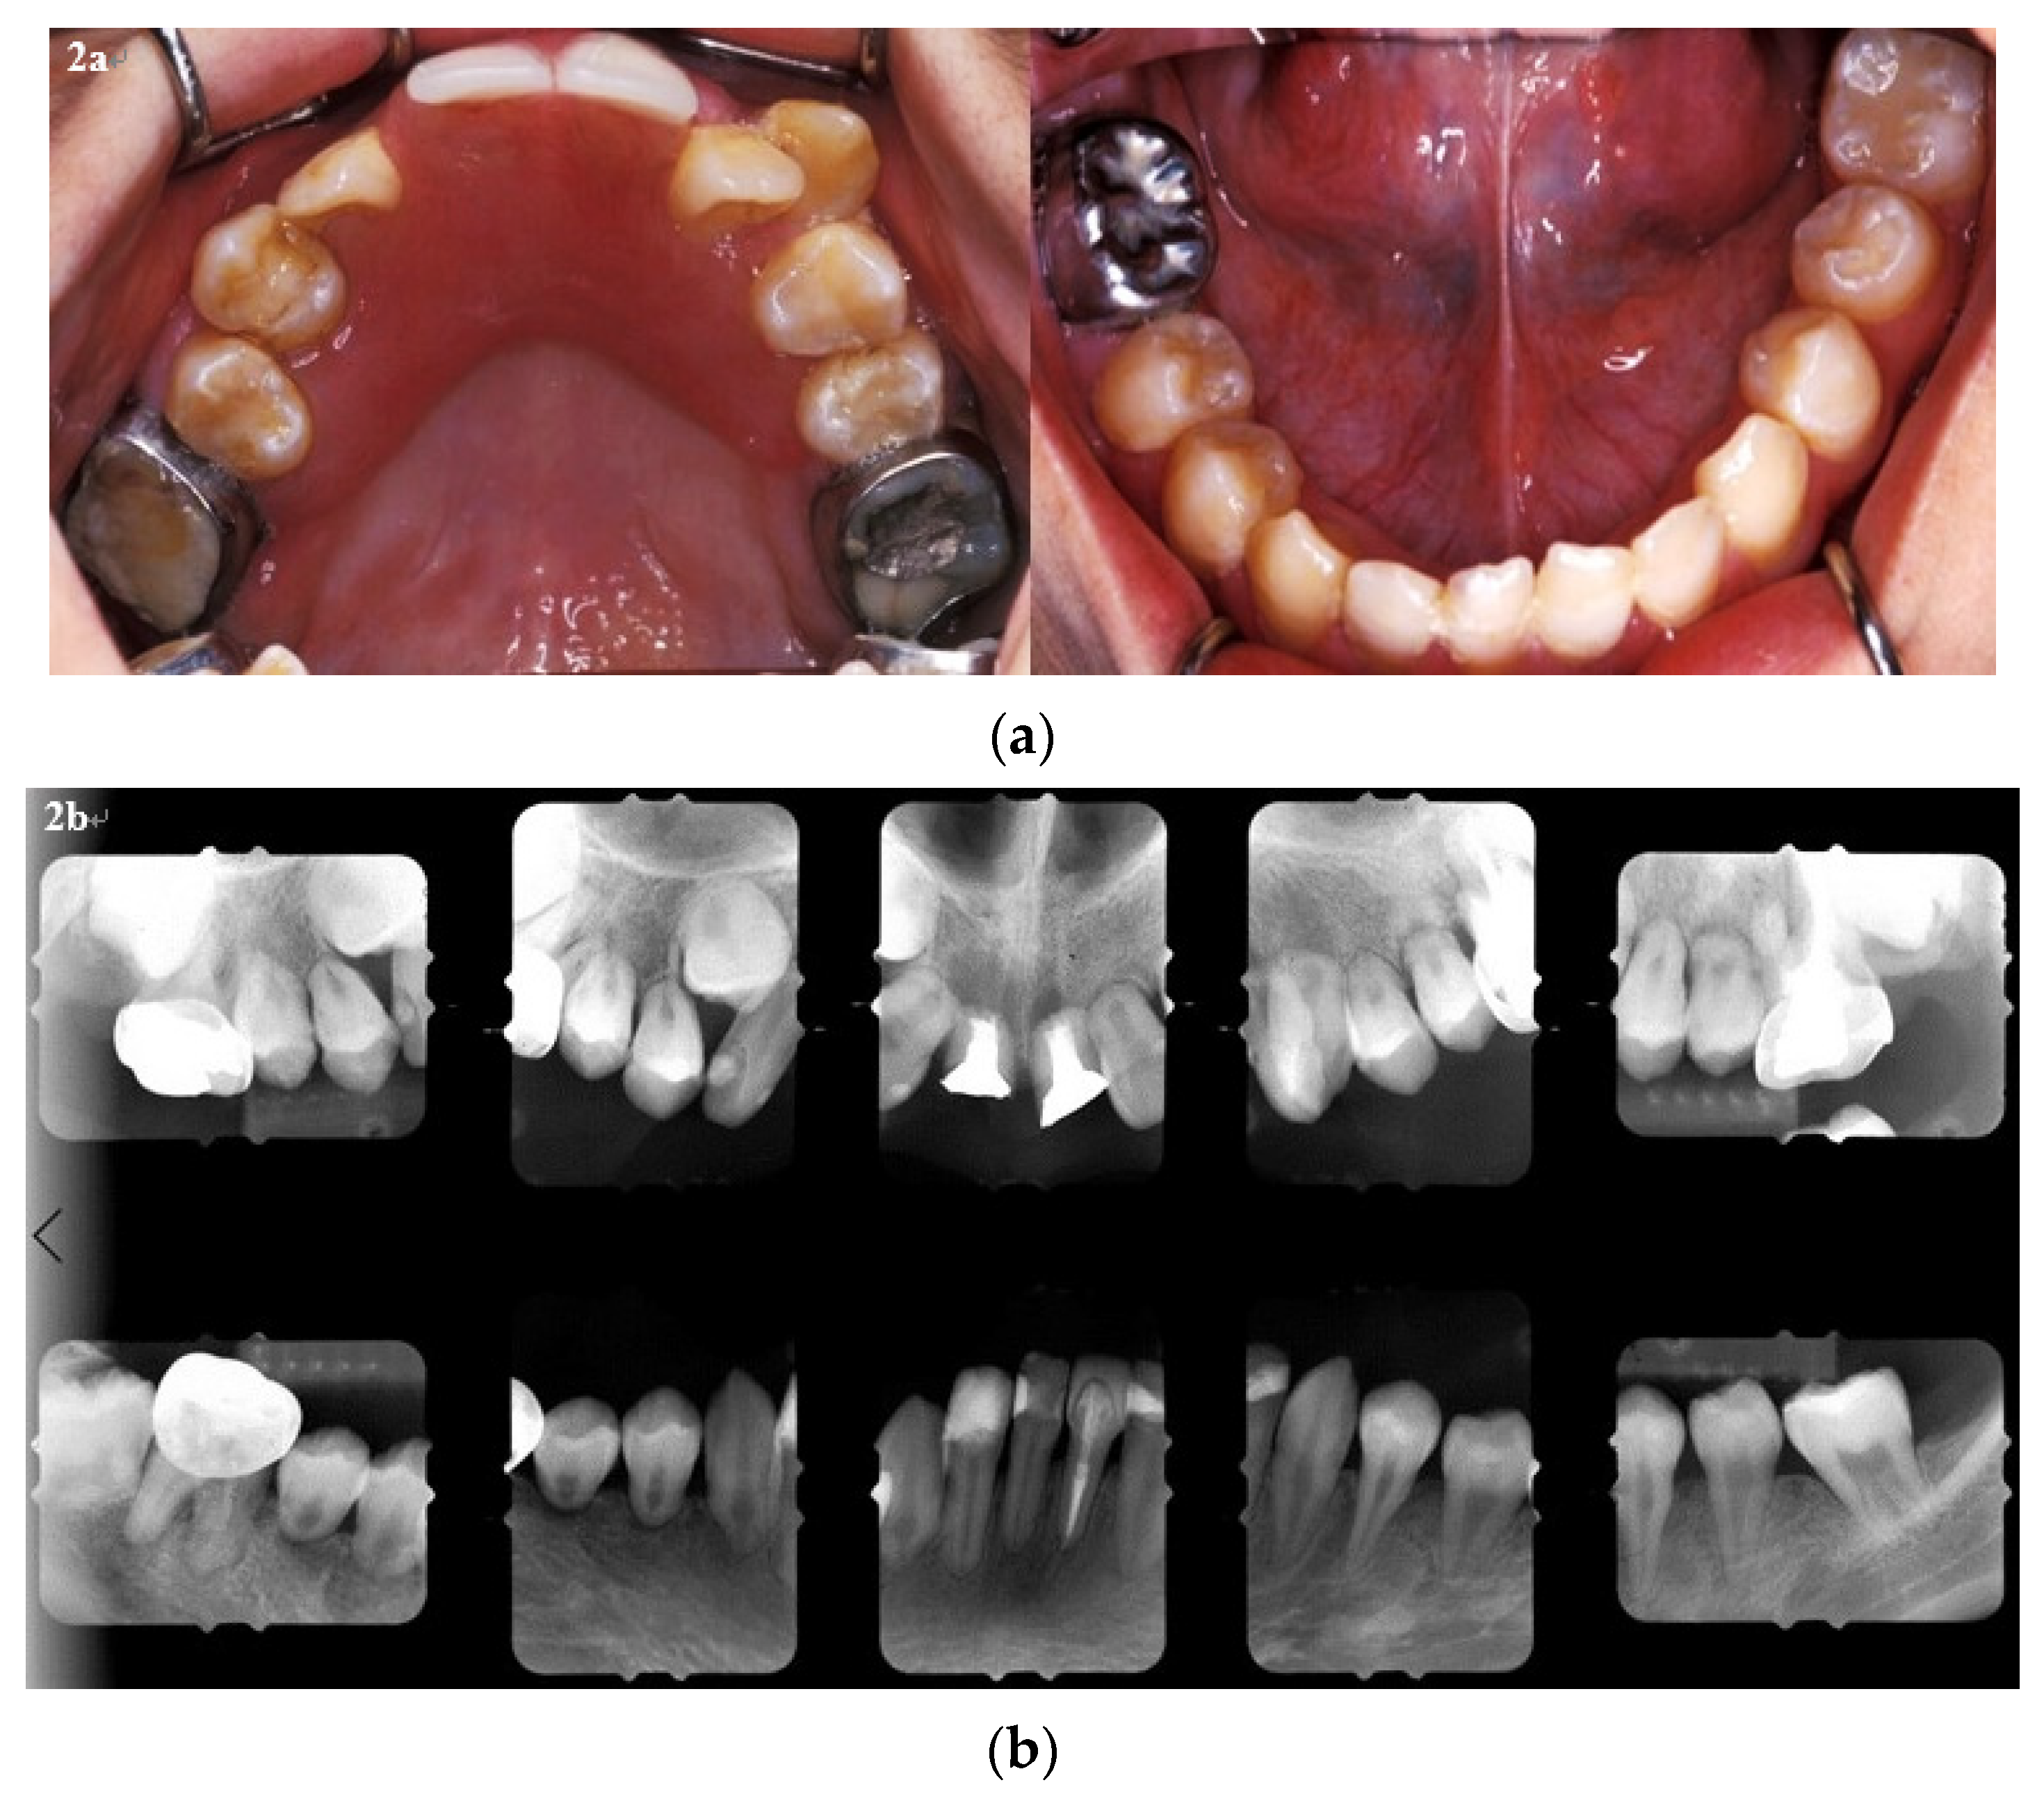

2. Case Report